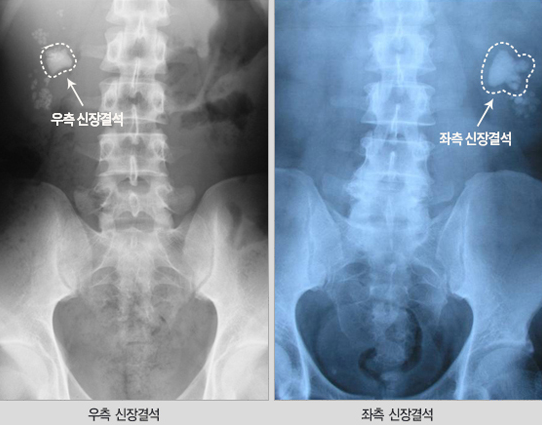

신장 결석은 비뇨의학과, 소아비뇨의학과에서 진료 받을 수 있습니다. 신장 결석이 의심된다면 신장 결석의 가족력, 과거력, 통풍 여부, 환자의 증상을 확인합니다. 이후에 방사선 촬영, CT, 초음파 검사 등으로 결석의 위치와 크기를 확인하고 필요시 혈액 검사, 소변 화학 분석 검사를 시행할 수 있습니다.

■ 영상의학적 검사

- 복부 방사선 촬영, 복부초음파, 복부 컴퓨터단층촬영(CT)등을 통해 신장결석의 위치를 확인 합니다. 필요시 조영제를 이용한 컴퓨터단층촬영(CT)을 시행하여 정확한 결석의 위치와 소변의 흐름을 막는지 여부 확인, 결석과 동반된 비뇨기계 변형을 알아볼 수 있습니다.